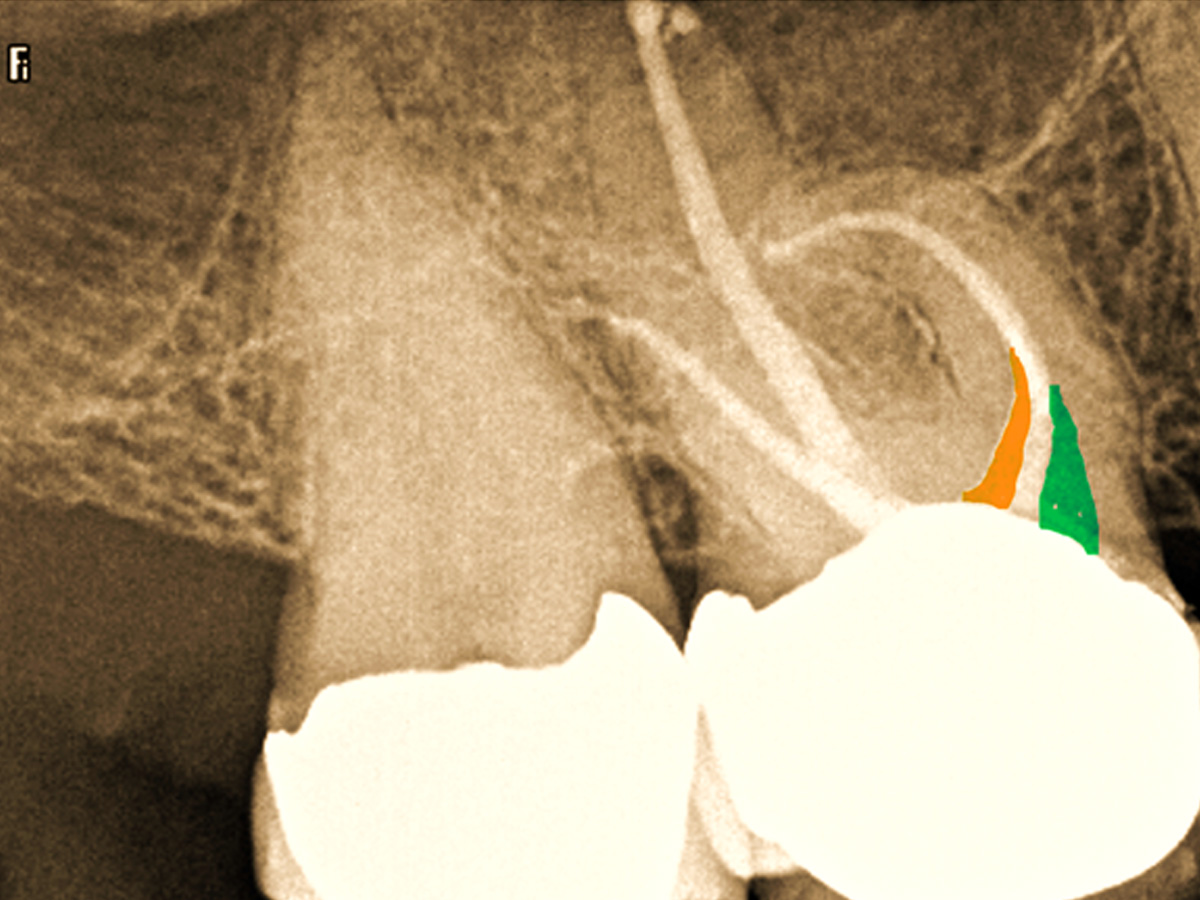

Abbildung 6

Mesiobukkal wurden zwei Kanäle aufbereitet, die apikal in einem Apex konfluieren.

Abbildung 7

Im koronalen Drittel wurden eine schonende Dentinabtragung (grüner Bereich) und Zugang zum Kanal durchgeführt. MB2 (oranger Bereich).